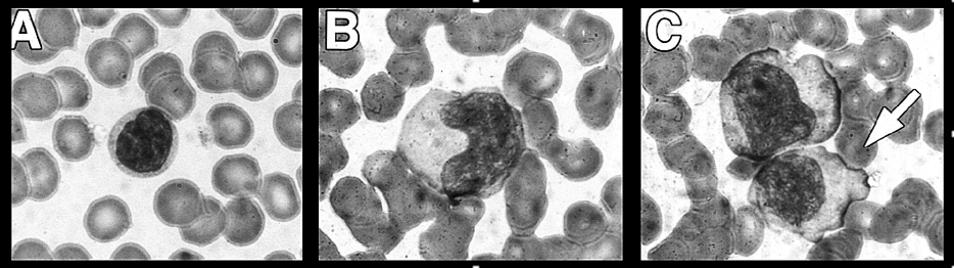

- Atypical lymphocytes [Fig] usually comprise 10-30+% of circulating lymphocytes.

Atypical Lymphocytes

A. Normal Lymphocyte

B. Enlarged, atypical lymphocyte with more cytoplasma and bilobed nucleous

C. So-called "Dutch Skirting" caused by red blood cells indenting lymphocyte outer membrane

Source: Paul G. Auwaerter, MD